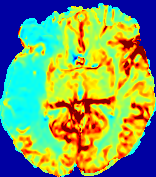

LesionRefer to captionRefer to captionRefer to captionRefer to captionRefer to captionRefer to caption𝐕rgbsubscript𝐕𝑟𝑔𝑏{\bf{V}}_{rgb}Refer to captionRefer to captionRefer to captionRefer to captionRefer to captionRefer to caption𝐕2subscriptnorm𝐕2{\|\bf{V}}\|_{2}Refer to captionRefer to captionRefer to captionRefer to captionRefer to captionRefer to captionRefer to caption3.53.53.52.82.82.82.12.12.11.41.41.40.70.70.70.00.00.0(mm/s)𝑚𝑚𝑠(mm/s)D𝐷DRefer to captionRefer to captionRefer to captionRefer to captionRefer to captionRefer to captionRefer to caption0.0200.0200.0200.0160.0160.0160.0120.0120.0120.0080.0080.0080.0040.0040.0040.0000.0000.000(mm2/s)𝑚superscript𝑚2𝑠(mm^{2}/s)Slice #1Slice #2Slice #3Slice #4Slice #5Slice #6

Figure 3: PIANO feature maps for one stroke patient, where the lesion is located in the left hemisphere. Top row: segmented stroke lesion region (white) on different slices, obtained from ISLES 2017. The corresponding slices for the PIANO feature maps are shown in the following rows.

For a better insight into an estimated velocity field 𝐕𝐕{\bf{V}} and diffusion field 𝐃𝐃{\bf{D}}, we compute the following maps: (1) 𝐕rgbsubscript𝐕𝑟𝑔𝑏{\bf{V}}_{rgb}: Color-coded orientation map of 𝐕=(Vx,Vy,Vz)T𝐕superscriptsuperscript𝑉𝑥superscript𝑉𝑦superscript𝑉𝑧𝑇{\bf{V}}=(V^{x},V^{y},V^{z})^{T}, obtained by normalizing 𝐕𝐕{\bf{V}} to unit length and mapping its 3 components to red, green, blue respectively; (2) 𝐕2subscriptnorm𝐕2\|{\bf{V}}\|_{2}: 222 norm of 𝐕𝐕{\bf{V}}; (3) D𝐷D: scalar field in Eq. 5.

Fig. 3 and Fig. 4 show the PIANO feature maps estimated from two ISLES 2017 patients: all are highly consistent with the lesion in both cases. Details of the blood flow trajectories are revealed in 𝐕rgbsubscript𝐕𝑟𝑔𝑏{\bf{V}}_{rgb} by the ridged patterns and the sharp changes of colors in the unaffected (right) hemisphere, while the flat patterns appearing within the lesion provide little directional information about the velocity and indicate low velocity magnitudes. Velocity magnitudes are more directly visualized via 𝐕2subscriptnorm𝐕2\|{\bf{V}}\|_{2}, from which one can easily locate the lesion where 𝐕2subscriptnorm𝐕2\|{\bf{V}}\|_{2} is low. D𝐷D also indicates lower diffusion values in the lesion, though with less contrast potentially due to the fact that it captures the accumulated effect of CA diffusion at the voxel-level.